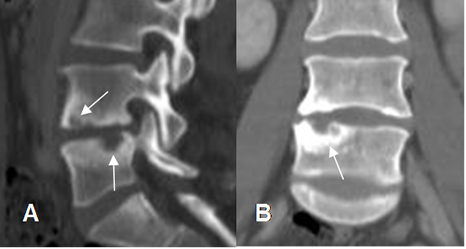

La destrucción de las placas terminales es un hallazgo típico de infección. (31). (Fig 138 A y B).

En TAC los cambios iniciales pueden pasar desapercibidos, por el efecto del volumen parcial de los cortes axiales, que se evita realizando reconstrucciones sagitales y coronales. (34).

Fig 138 A. Espondilodisquitis.

A: Rx lateral. Disminución de algunos espacios intervertebrales. En la parte inferior de L3, hay erosión de la placa terminal.

B: TAC axial en ventana de tejido, C: TAC axial en ventano ósea y D: TAC reconstrucción coronal. Destrucción de la placa terminal inferior de L3, con masa de tejidos blandos y que corresponde a espondilodisquitis.

Fig 138 B. Espondilodisquitis.

A: TAC reconstrucción sagital y B: TAC reconstrucción coronal. Disminución del espacio intervertebral, con erosión de las placas terminales.